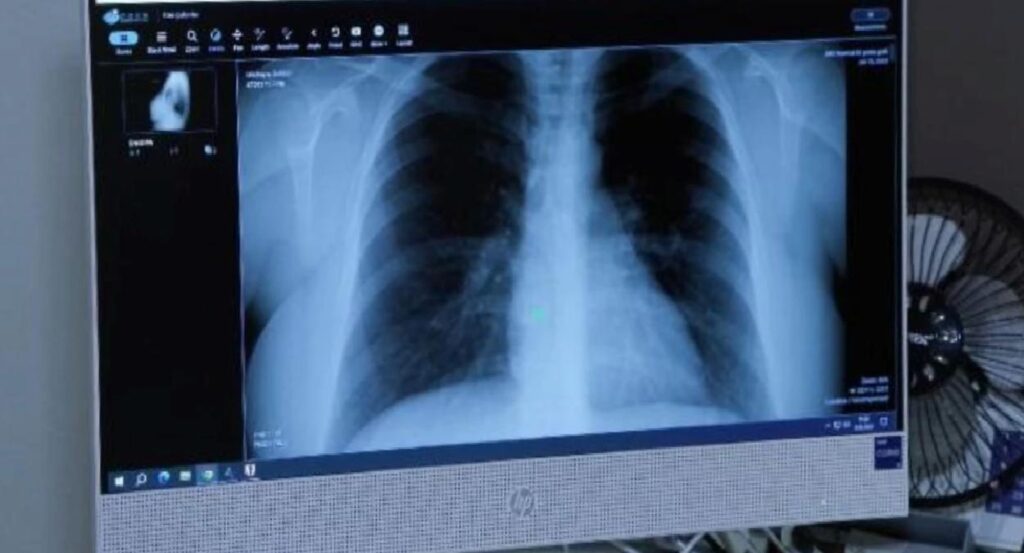

Birleşmiş Milletler (BM) İnsani İşlerden Sorumlu Genel Sekreter Yardımcısı Martin Griffiths, Gazze'de sıhhat sisteminin çöktüğünü...